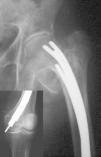

ComplicacionesSe produjo migración distal de los clavos en 104 pacientes (28%), siendo mayor de 2 cm en 67 casos (18%) (fig. 3). La correlación clínica entre migración, dolor y palpación de los clavos se observó en 41 casos (11%). La rotación externa de la pierna intervenida mayor de 10° se dio en 93 casos (25%). Dolor en rodilla en 86 pacientes (23%), de los cuales 28 no asociaban migración de los clavos mayor de 2 cm, ni palpación de los mismos. Migración proximal en 22 pacientes (6%) de los que 12 tenían dolor inguinal. Pérdida de corrección del ángulo cérvico-cefálico en 19 casos (5%). Acortamiento mayor de 1,5 cm en 37 pacientes (10%). Infección de la herida quirúrgica en 12 pacientes (3%). Parálisis del nervio ciático poplíteo externo en un caso. Rotura de los clavos en un caso. Pseudoartrosis un caso. Fractura supracondilea de fémur un caso.

Figura 3. Migración distal de clavos de Ender en una fractura pertro cantérea inestable, en un paciente con altas demandas funcionales.